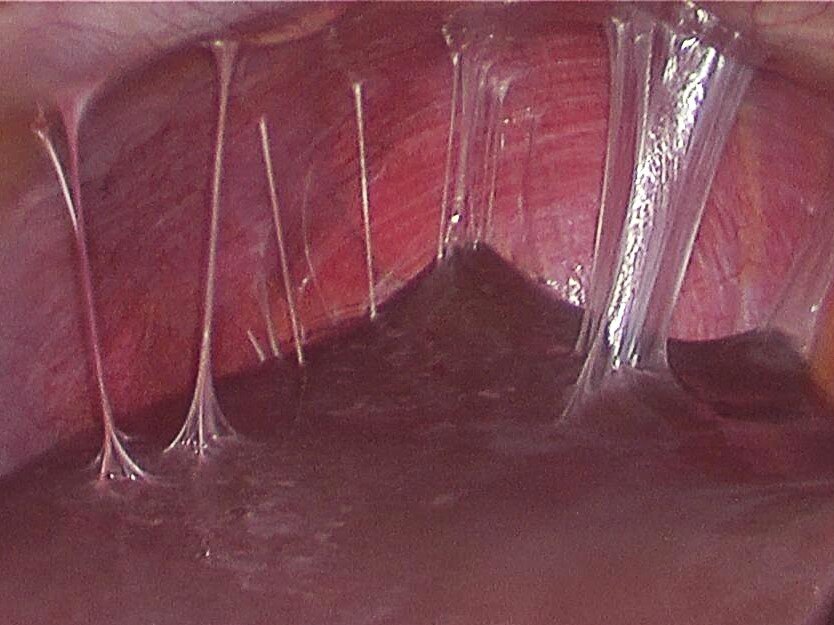

Внутриматочные синехии (МС) могут формироваться из-за травмы эндометрия во время миомэктомии, они негативно влияют на репродуктивную функцию. Однако частота и степень выраженности МС после МЭ плохо изучена. Механизм формирования МС все еще во многом непонятен и скорее всего является многофакторным. Травма базального слоя эндометрия обычно рассматривается как инициирующий фактор в формировании МС. Гистероскопическая МЭ (ГСМЭ) очевидно ассоциирована с формированием МС, причем монополярная энергия и множественные узлы на противоположных стенках ассоциированы с бОльшим риском появления МС. Однако не так много данных о влиянии лапароскопических или лапаротомических операций; более того, нет исследований, в которых проводилось бы сравнение частоты МС после разных техник удаления миомы. Эта информация важна для определения тактики ведения пациенток.

Первичными исходами было наличие и степень тяжести ВМС, вторичными – определение факторов риска их образования, определяемых при ГС или ГСГ. Выбор между ГС и ГСГ был на усмотрение лечащего врача в зависимости от типа страхования, предпочтений пациентки, клинических данных. Степень выраженности спаек внутри матки оценивалась двумя исследователями как "легкая", "средняя", "тяжелая" в соответствии со шкалой, ранее описанной March et al.

Офисная гистероскопия проводилась с 5 по 12 д.м.ц., как минимум через 3 месяца после МЭ, использовался гибкий эндоскоп 3,1 мм (Olympus HYF-XP, Olympus Surgical Technologies America).

МС были выявлены у 16 пациенток (9,3%): МИХ – 8,6% , ЛТМЭ – 7,8%, ГСМЭ – 11,8% (Р=0,8), степень тяжести отражена на рисунке 1.

Рис. 1. Частота формирования МС разной степени в зависимости от методики МЭ